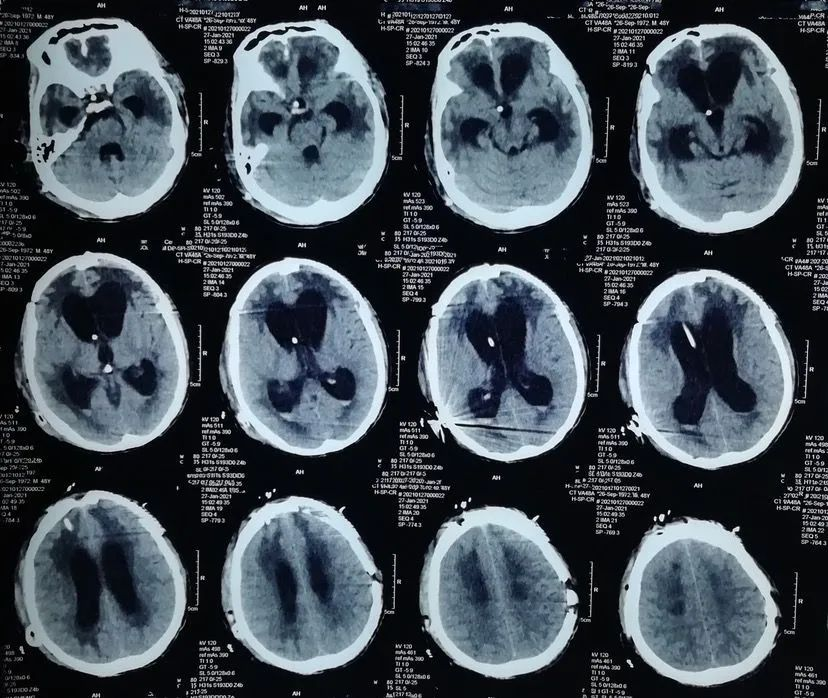

给予行左额颅骨成形术,术后双侧硬膜下积液消失,但出现脑积水,也就是脑外积水转为脑内积水。